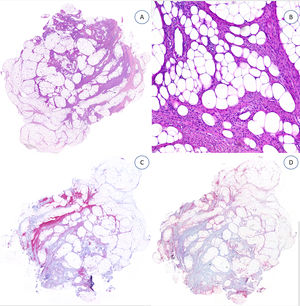

Los casos se caracterizaban por presentar una morfología trifásica con una proporción variable de tejido fibroblástico/miofibroblástico, mesenquimal inmaduro y adiposo maduro en dermis o subcutis (figs. 1, 2 y 3). En términos generales, las lesiones se describieron como mal delimitadas (fig. 1).

A) HFI dérmico e hipodérmico B) A mayor aumento, bandas densas de tejido fibroso proyectándose en el tejido graso maduro. C) Trabéculas entrelazadas de tejido fibroso que presentan colecciones de fibrocitos de aspecto inmaduro en patrones de espiral. D) Componente mesenquimatoso inmaduro basófilo entremezclado con tejido fibroso.

HFI: hamartoma fibroso de la infancia.

Las trabéculas fibrosas varían en grosor y disposición, y contienen haces de células en forma de huso dispersos aleatoriamente entre haces de colágeno (con colecciones de fibroblastos de aspecto inmaduro, formando patrones en espiral) (fig. 2). Los nódulos mixoides de tejido mesenquimal inmaduro estaban compuestos por células redondas o estrelladas primitivas, indiferenciadas, dispuestas libremente o embebidas en un estroma mixoide (fig. 3). Finalmente, podemos observar áreas de tejido adiposo maduro (figs. 1 y 2).

La proporción relativa de cada componente era muy variable. Uno de ellos se consideró «predominante» si ocupaba igual o más del 45% de toda la lesión. Siete casos presentaron una distribución equitativa; en nueve, el componente predominante fue el adiposo, y en cuatro, fue el fibroblástico. Encontramos un predominio significativo del tejido mesenquimal inmaduro en uno de nuestros pacientes (tabla 1).